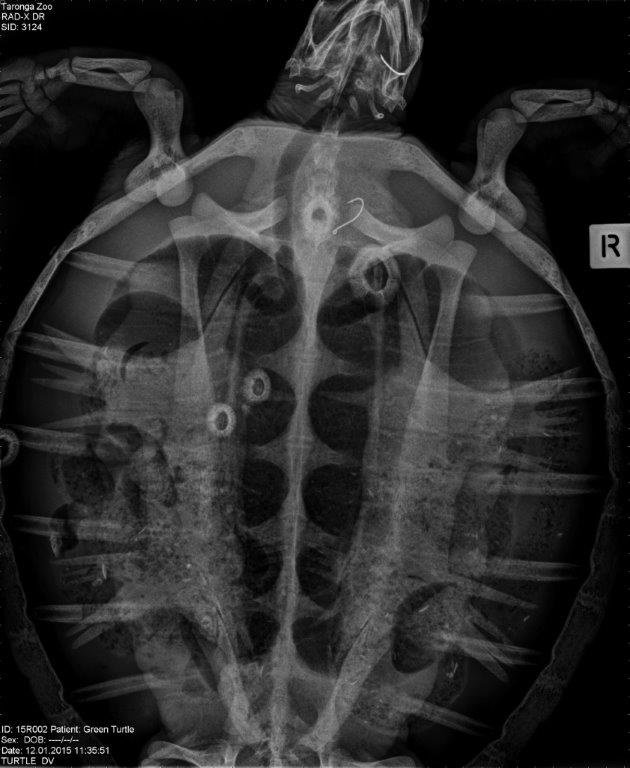

A juvenile Green Sea Turtle is recovering in the Wildlife Intensive Care unit after being rescued with hooks lodged in its mouth, flipper and in its gut. There was also a large amount of fishing line throughout the turtle’s intestines.

Taronga Wildlife Hospital Manager, Libby Hall, said: “A lot of the time people mostly think of the damage the fishing hooks do, but where there’s a hook, there’s a line. Fishing line is very strong and cuts its way through the digestive system of marine animals, which has potentially fatal consequences.”